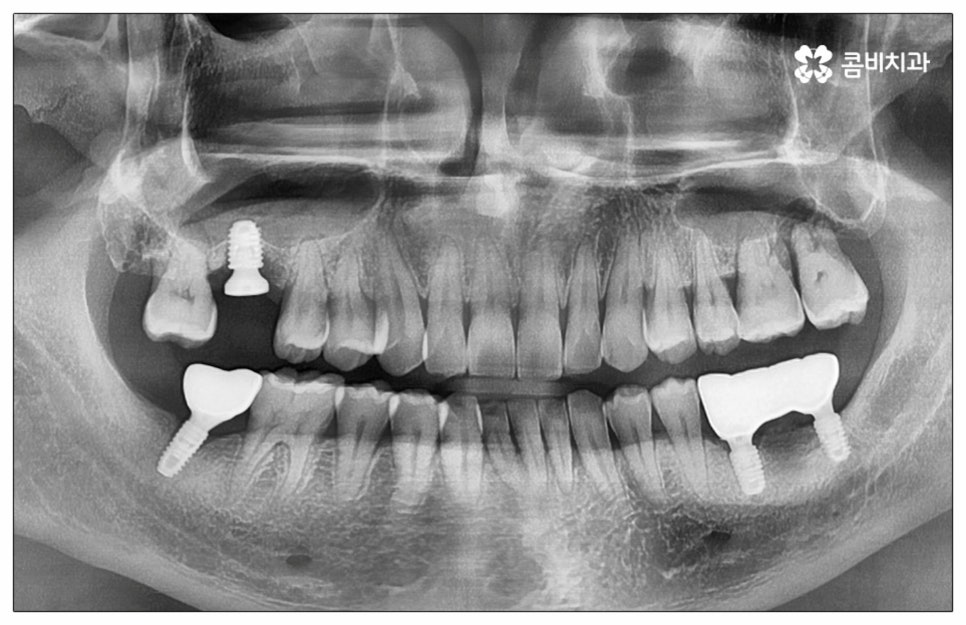

예전에는 이런 상황에서 틀니를 많이 이용하였으나 저작력 회복이 본래 자신의 치아 대비 20~30% 정도 밖에 되지 않고 잦은 탈락 위험 및 이물감, 잇몸을 눌러 장기적으로 잇몸뼈가 내려앉을 수 있다는 점 등 여러 가지 불편함이 있어 요즘은 임플란트 시술을 선호하시는 분들이 더 많아지고 있어요. 임플란트란 인체에 무해하며 잇몸뼈와 잘 결합하는 인공 치근을 잇몸뼈에 직접 식립하고 그 위로 기둥이 되는 중간 지대주와 치아 머리가 되는 크라운 보철물을 연결하여 인공 치아를 만들어 주는 시술을 말하는데, 자연 치아의 80% 정도 저작력 회복이 가능하기 때문에 식사를 할 때 음식을 크게 가리지 않아도 된다는 점 그리고 심미적으로 봤을 때 주변 치아와 자연스럽게 어우러진다는 점 때문에 각광을 받고 있습니다. 게다가 건강 보험 가입자이면서 만 65세 이상 부분 무치악 환자라면 평생 임플란트 2개까지 보험 적용을 받아 비용 부담을 줄일 수 있기 때문에 더욱 더 수요가 늘어나 이제는 치아 상실에 대체하는 대표적인 방법으로 임플란트 시술이 꼽히고 있는데요.

많이 대중화 되었다고 해도 임플란트 수술 자체가 술자의 숙련도에 크게 영향을 받는 복잡하고 고난도의 진료인 것은 틀림이 없기 때문에 담당 의료진이 해당 분야 임상 경험이 풍부한지, 뛰어난 기술력과 노하우를 가지고 있는지 꼼꼼하게 체크해 보실 필요가 있어요. 특히 노년층의 경우 당뇨, 고혈압 등 만성 질환을 앓고 있는 경우가 많아 혹시 상시 복용하고 있는 약이 있는지, 현재 환자 개개인의 상태는 어떤지, 사전 처치가 필요한 부분은 없는지 등등 수술 조건을 좀 더 까다롭게 평가한 후 환자분들과 이에 대해 충분히 상담하고 맞춤형 치료 계획을 세워 진행해야 하며 이를 위해 3D CT 와 같은 디지털 검진 장비를 통해 구강 내부 구조를 면밀하게 살피고 방대한 임상 데이터를 축적한 정품 임플란트 재료를 이용하여 연령이나 회복 정도를 살펴보면서 체력적 부담을 줄이는 방향으로 무리하지 않게 식립하는 것이 무엇보다 중요하다고 할 수 있습니다.

우리 나라 건강보험임플란트 제도는 언제부터 시작이 되었을까요? 임플란트 관련 보철급여제도는 2014년 만 75세 이상 2개 적용을 시작으로 점차 대상을 확대해 왔는데요, 2016년 이후 적용 나이가 만 65세로 낮아졌고 2018년 이후 본인 부담 비율도 30% 까지 인하되었는데 이러한 적용 나이 확대와 본인 부담률 인하로 인해 2019년부터 건강보험임플란트 급여 적용 시행 건수가 급격히 증가하였다고 보고 되고 있습니다. 여기서 30% 라는 것은 일반적인 만 65세 부분 무치악 환자를 기준으로 한 것이고 만약 차상위 대상이나 희귀난치성 환자, 만성질환자라면 건강보험임플란트 본인 부담 비율이 더욱 낮아지니 자신이 어디에 해당하는지 자세하게 알아보시고 도움받아 보시면 좋을 거예요.

이때 추가 수술은 비급여 항목으로 건강보험임플란트 대상에서 제외되니 이에 대해서도 꼼꼼하게 살펴보시고 정밀 검진 후 담당 의료진과 자신의 상황에 대해서 충분하게 상담해 보시길 권유드리고 있습니다. 추가 수술의 대표적인 예로는 뼈이식 수술이 있는데요. 이것은 임플란트를 식립할 때 바탕이 되는 잇몸뼈의 높이나 폭, 밀도 등이 부족하다면 먼저 이를 보충해 주고 나서 임플란트를 심어주는 과정을 의미하며 같은 이유로 식립 성공률이나 장기적인 안정성을 높이기 위해 꼭 필요한 사전 처치, 즉 상악동 거상술 및 치주 질환 관련 수술 등을 먼저 해야 한다면 이 역시 추가 수술의 범주로 들어가니 자신의 상황에 대해서 상세하게 알아보실 필요가 있어요.